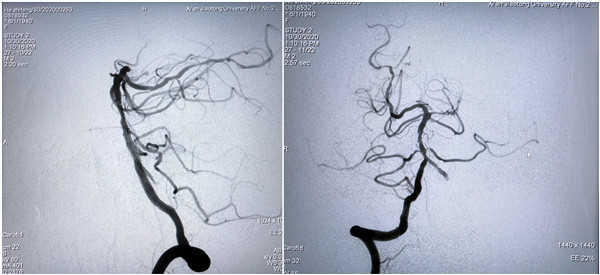

术中北京天坛医院神经介入科莫大鹏教授、中国医科大学第四附属医院神内高连波教授通过远程直播平台实时点评,对此次直播的手术难度、技术细节等进行点评、交流。历经一个多小时,手术顺利完成,圆满取得预期效果。此次直播利用我院新引进的西门子双C臂血管造影机,充分展示了新型血管造影机在神经介入方面的优势,展示了我院神经内科规范、先进的介入治疗方式和技巧。

此次手术演示直播,我院神经内科选择的手术是神经介入难度大、风险高的基底动脉狭窄支架成形术,而且患者系79岁高龄,合并高血压、糖尿病等多种并发症,更增加了手术的风险和难度。术前经过全科讨论,充分准备,对患者病情进行详细评估,尤其是做了我科在国内率先开展的椎基底动脉颅内段平行扫描的BPAS-MRl检查。张主任提前与麻醉科吕建瑞主任充分沟通,在影像科、麻醉科的支持下,由麻醉科赵红霞医师实施全麻,由张桂莲教授主刀,张茹副教授做学术导播全程讲解,展淑琴教授作为一助,张磊医生做二助,护士张倩和蒋鹏鹏辅助手术,范松华博士进行病例汇报。